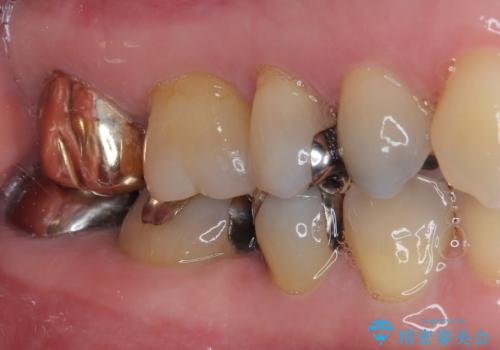

ハイブリッドインレーの装着時には、唾液の侵入を防ぐために、ラバーダム防湿を行いました。

見ため、機能面ともに違和感なく大変喜んでいただきました。

今後はメンテナンスで通ってもらいながら経過観察していく予定です。